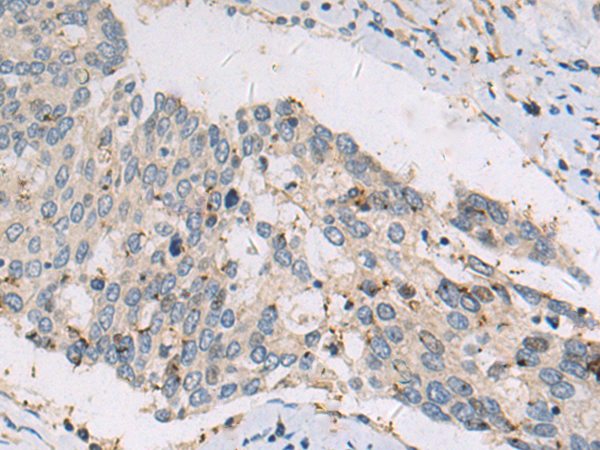

分类: 科研抗体货号: P10607别名: Prp5; PRPF5应用: IHC反应种属: Human, Mouse, Rat